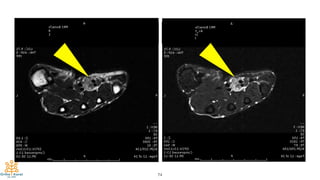

Case #2

47

15-year-old

Mass at thenar area and wrist

Progressive numbness of thumb,

index and middle finger

48

49

50

51

Final Diagnosis:

Lipofibromatous Harmatoma